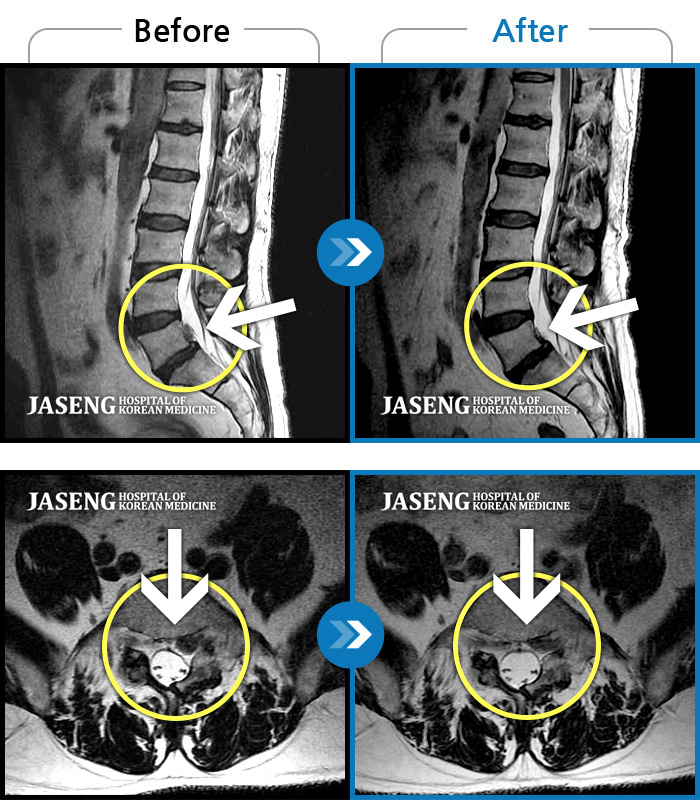

처음 내원 시 허리와 좌측 골반이 많이 아프고, 좌측 다리로 저림과 감각 저하가 있어서 보행이 원활하지 못했으며, 야간통으로 잠도 못 자고 통증 심하여 정상적인 활동이 힘든 상태셨습니다.

2023.09.16 ~ 2024.09.24